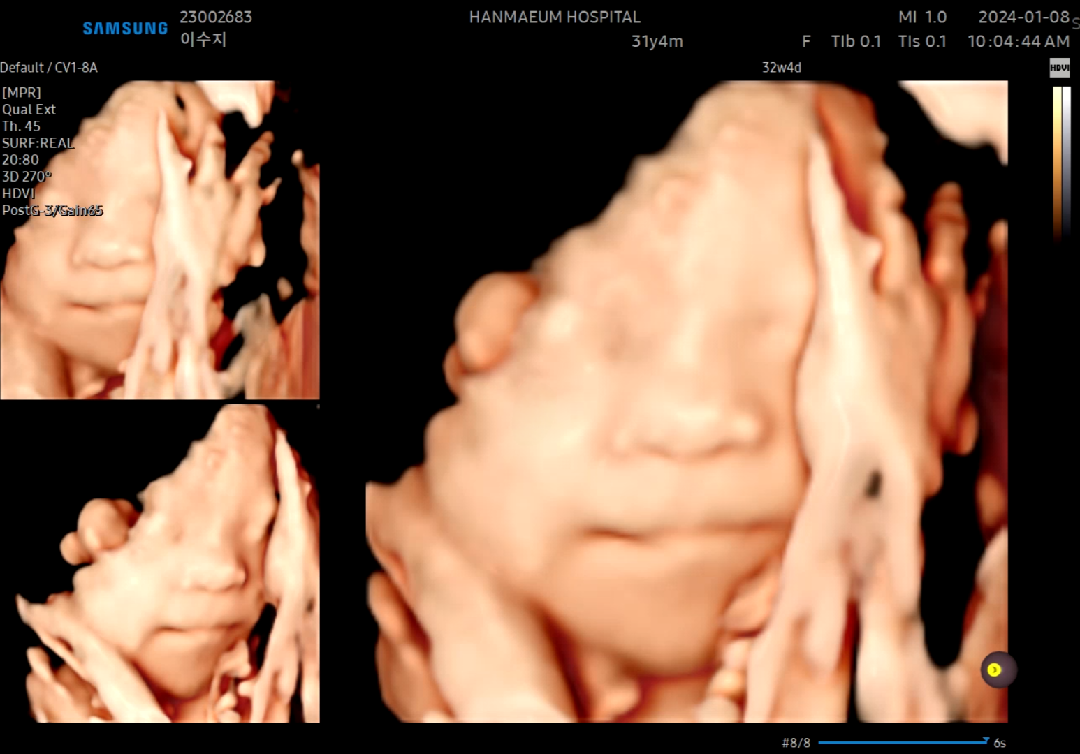

32주4일차 마지막입체초음파!!얼굴보기성공!!

울 애기 태어나기전 마지막 입초 보고왔네요! 또 얼굴앞으로 지나가는 탯줄때문에 애먹었는데 입초쌤의 노력끝에 깨끗한 얼굴도 보고 저렇게 손올리고 웃는 모습까지 보고왔어요😍 남편이랑 같이 가서 잘보여주길 기도하며 갔는데!! 저렇게 협조를 잘해주다니!!기특한녀석❤ 하....웃는거 진짜 너무 귀여워요ㅠㅠ 웃는입초라.....귀한거맞죠?!❤❤❤ 얼른 보고싶은 도치맘이랍니다ㅠㅠㅎㅎ